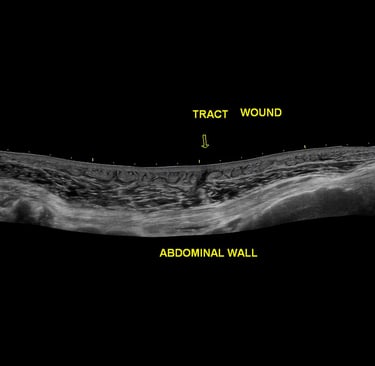

General Scans

Comprehensive radiological ultrasounds tailored to your health needs.